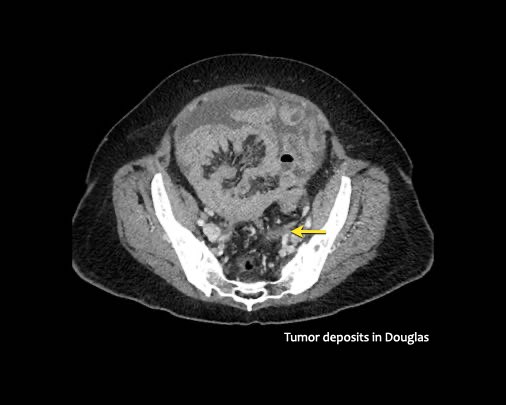

Ở vùng chậu, vị trí quan trọng nhất là túi cùng trực tràng-tử cung và trực tràng-bàng quang (túi cùng Douglas).

- Túi cùng trực tràng-tử cung và trực tràng-bàng quang (túi cùng Douglas)